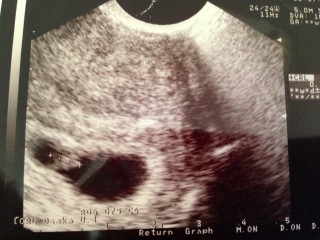

先週の5週の時はCRL1.6mmで今回はCRL8.5mmまで成長してて心拍もしっかり確認出来た!大きさから言って6週後半でしょうと!チカチカ点滅してる姿だけでも可愛い!胎嚢は37.8mmまで成長(*^_^*)狭くないか?と思ったけどエコーの当て方らしい(*^_^*)

1人目の時は、6w0dで心拍確認出来たため、先週6w1dでは、今見えたんだけど…と、その後少し時間をかけ、診てくれた中で、チラッと見えたか見えないか…

心拍も出始めは、ゆっくりだから~まあ、もう一度ちゃんと見たいですね、との言葉に不安になりましたが、今日無事確認出来、ひとまず安心せました。